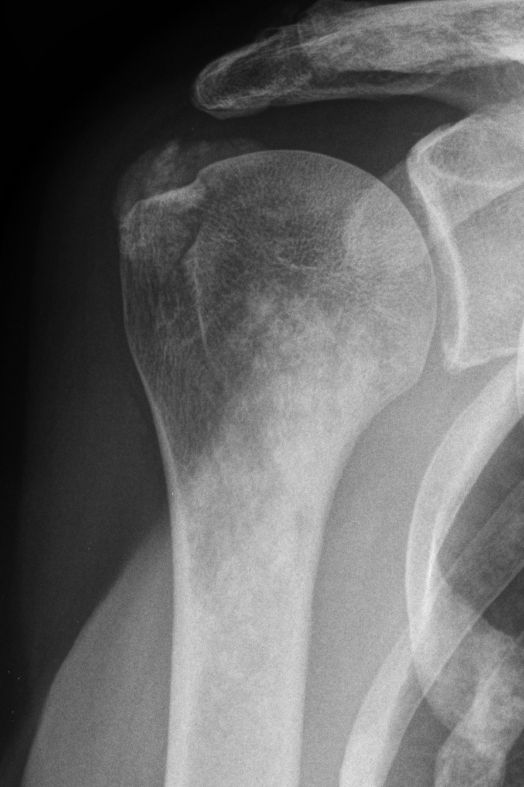

70-jährige Frau mit ossär metastasiertem

Mammakarzinom. Wolkige Verkalkungen im Humeruskopf. Osteoblastische Metastasen.![]() |